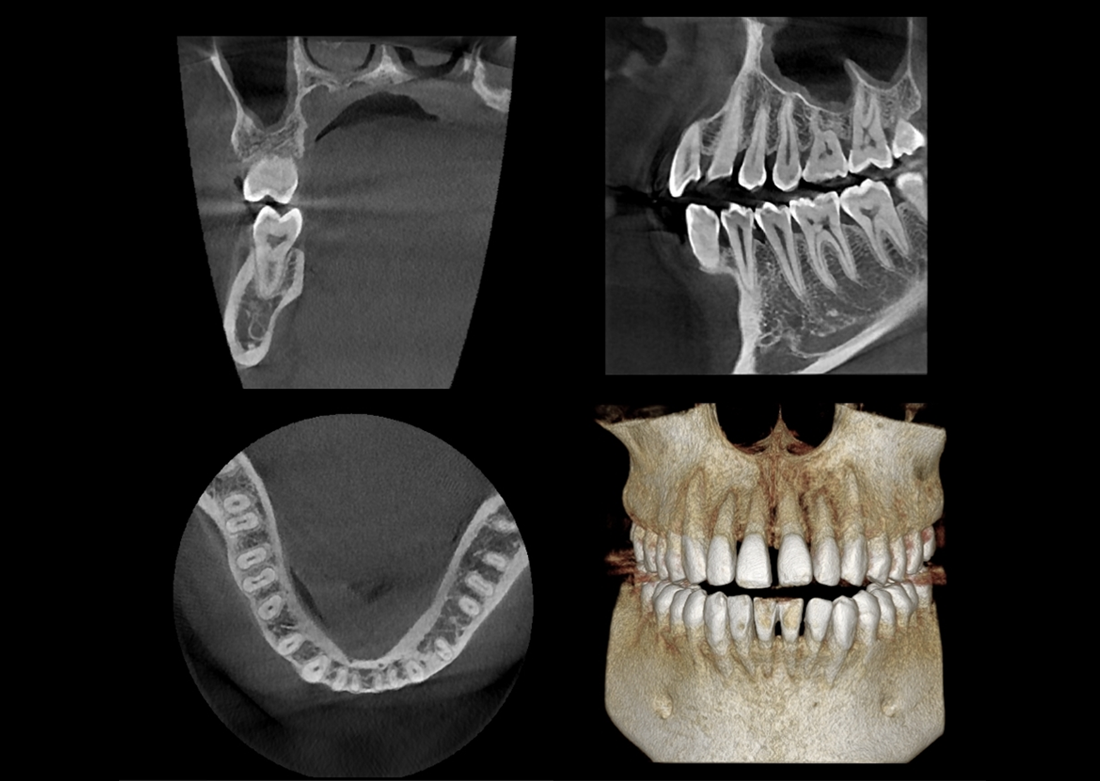

KLİNIKAI KÉPEK

Kiváló diagnosztikai képalkotás több éves tapasztalattal és szakértelemmel.

A Genoray büszkesége, amelyet világszerte elismernek és szeretnek.